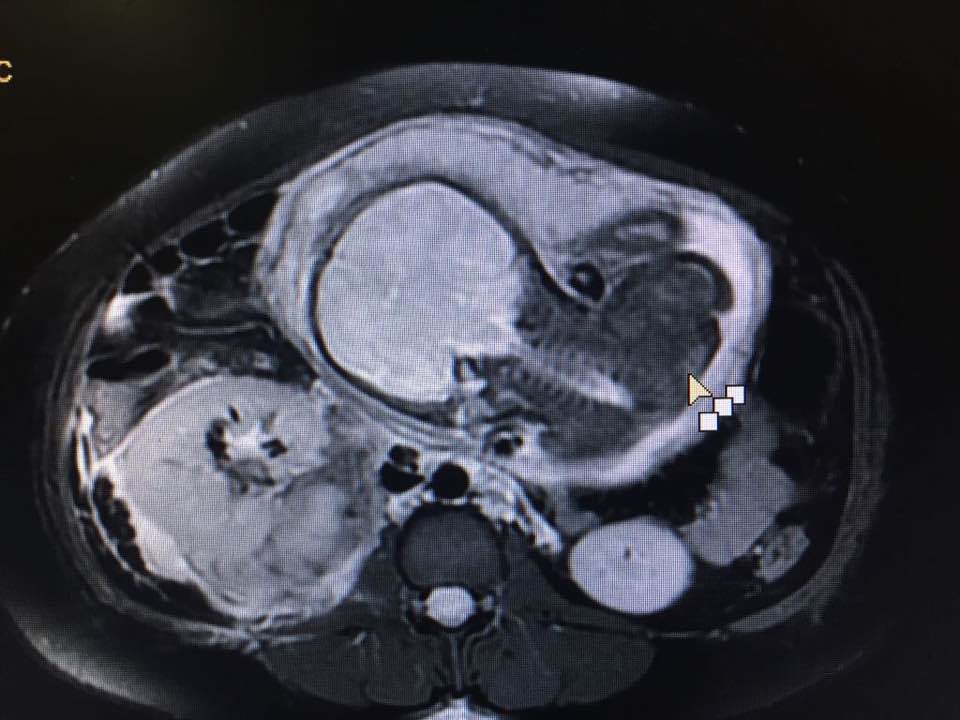

A 33 weeks pregnant patient with right renal Angiomyolipoma presented with pain in right flank. In MRI it was found that the tumour in her kidney was bleeding. She was immediately shifted to operation-theatre and Cesarean was operated with right radical Nephrectomy and salvaged. Now both mother and baby doing fine.